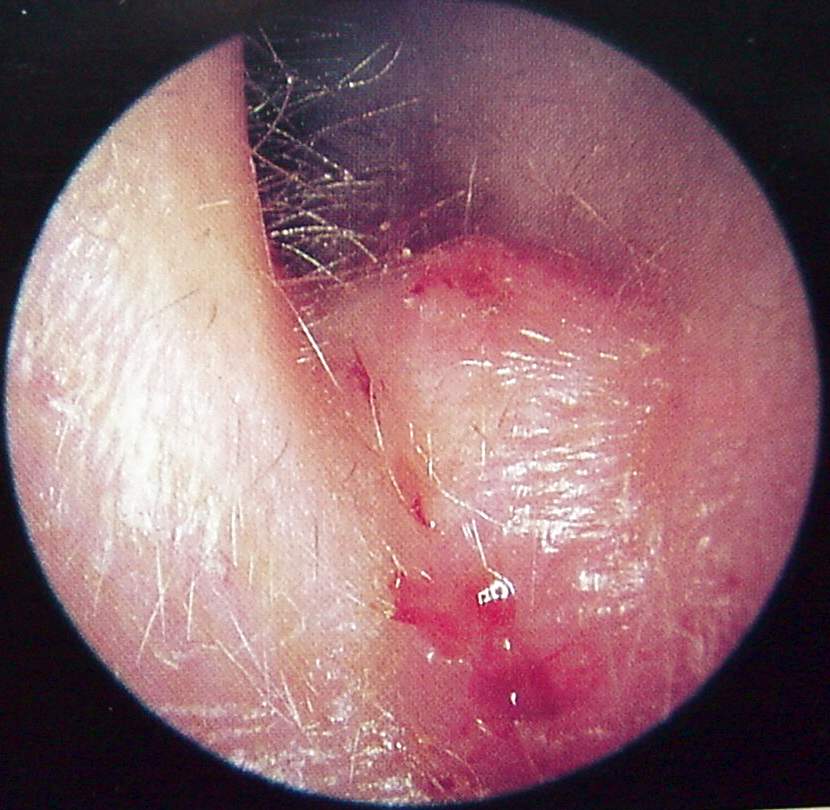

Ear Clinical Photos for Static Stations